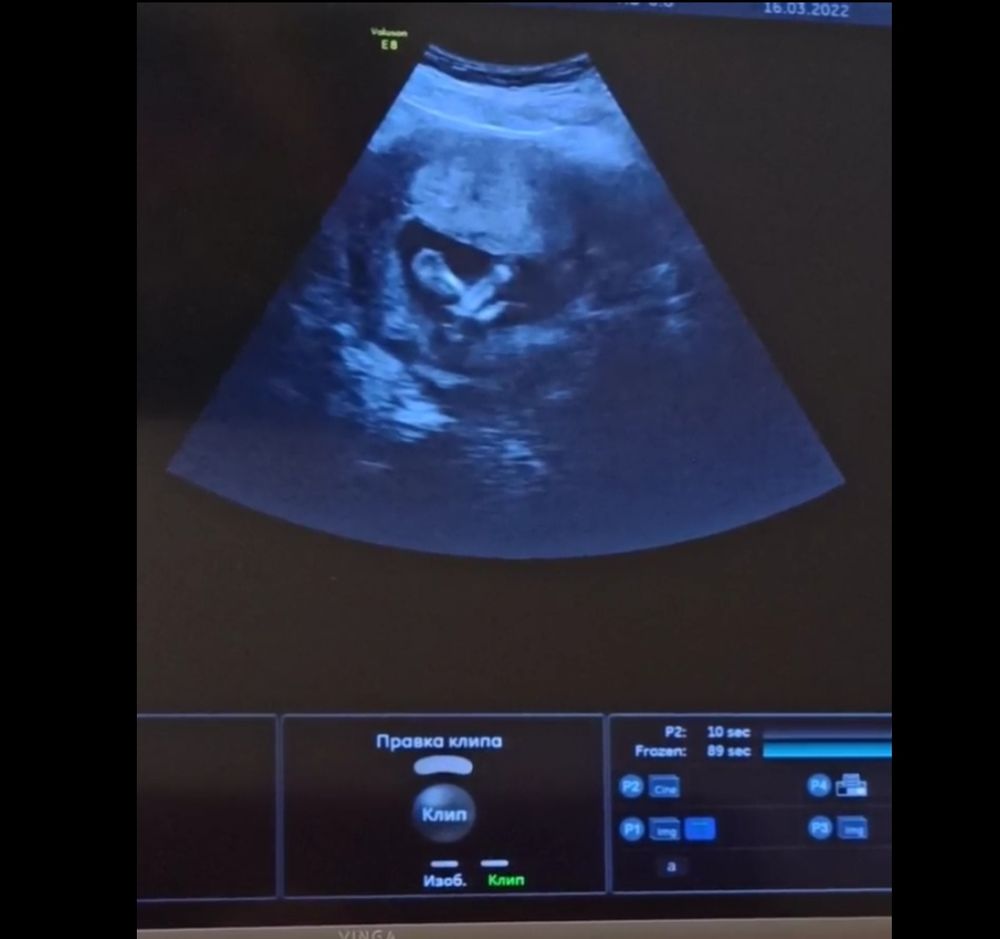

16-ая неделя, наконец-то встретились!

16.03.2022

Какой необычный интересный ракурс- с личиком) Берегите себя и своего крошку! Прекрасно, что вы все вместе!

Какой красивый малыш)) Легкой беременности! Берегите себя.